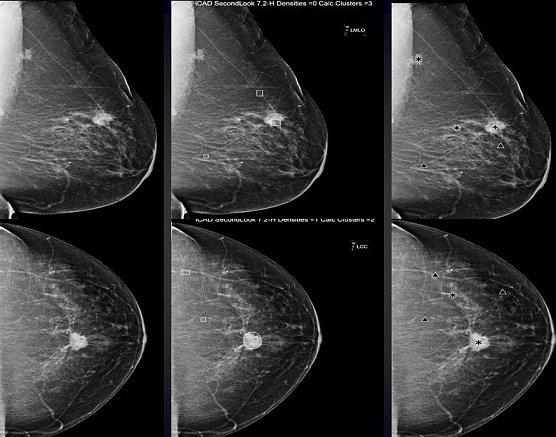

Hier sieht man links eine Röntgenaufnahme der weiblichen Brust mit einem bösartigen Tumor sowie in der Mitte und rechts jeweilige computerbasierte Analysen, die mit verschiedenen Programmen (R2 und iCAD) jeweilig auffällige Strukturen in der Röntgenaufnahme (Mammographie) markieren und für den Befunder hervorheben, Verdichtungen mit Stern bzw. Kreis sowie auffälligen Mikrokalk (kann auch mit Brustkrebs assoziiert sein) mit Dreieck bzw. Viereck (je nach Hersteller der Software unterschiedlich).